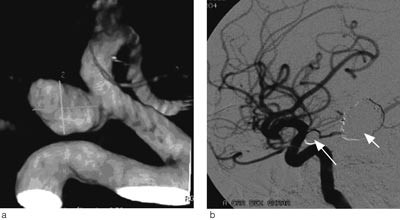

Universitetssykehuset er regionsykehus for vel 470 000 innbyggere i Helse Nord. Nevrokirurgisk avdeling har siden 1986 utført kirurgisk behandling av intrakraniale aneurismer (fig 1) (11). Endovaskulær behandling ble introdusert i 2000 (fig 2).